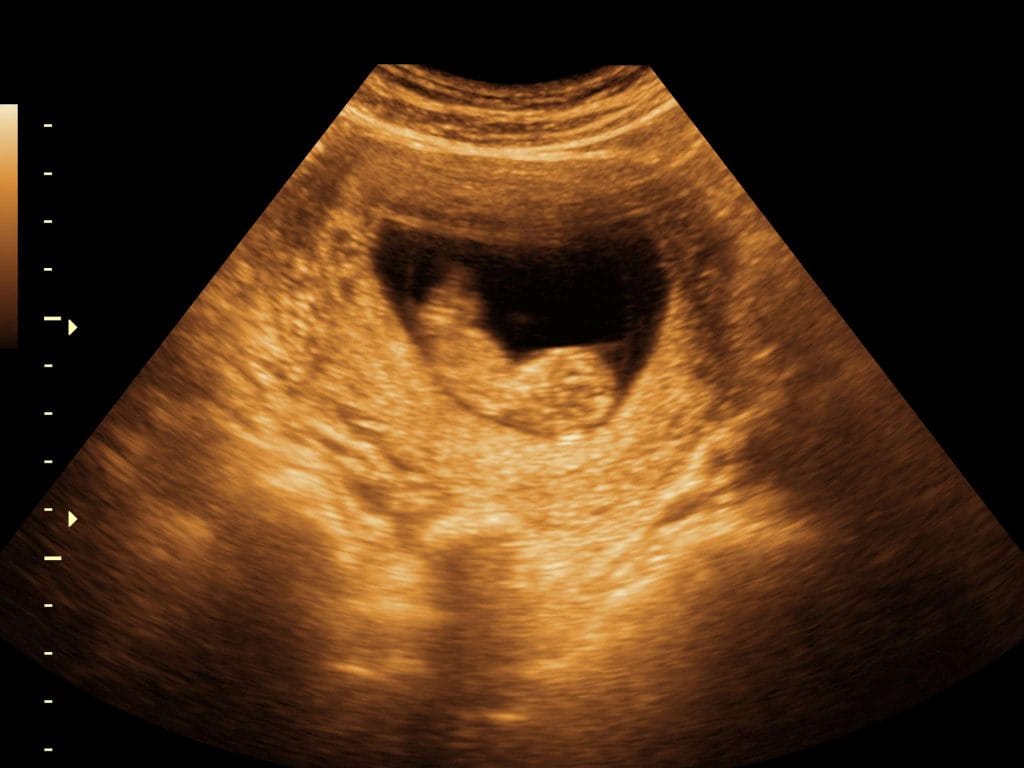

11. Haftada Ultrason Görüntüsü Nasıl Olur?

Gebeliğin 11. haftasında yapılan ultrason muayenesi, hem annenin hem de bebeğin sağlığı hakkında önemli bilgiler sunar. Bu haftada genellikle karından yapılan (abdominal) ultrason tercih edilir; ancak bazı durumlarda vajinal ultrason da hâlâ kullanılabilir.

Bebeğin Görüntüsü

- haftada bebeğiniz artık oldukça net bir şekilde görülebilir. Ultrason ekranında baş, vücut, kollar ve bacaklar ayırt edilebilir hale gelmiştir. Bebek hâlâ küçük olsa da, genel şekli insan formuna oldukça benzemeye başlamıştır. Bu haftada ultrasonla görülebilecek detaylar şunlardır:

- Baş-vücut oranı hâlâ büyüktür ancak dengeye gelmeye başlamıştır.

- Eller ve ayaklar gelişmiş ve parmaklar belirginleşmiştir.

- Bebek rahim içinde aktif şekilde hareket etmeye başlar ama bu hareketler anne tarafından henüz hissedilmez.

- Omurga çizgisi net bir şekilde görülebilir.

- Kalp atışları saniyede yaklaşık 2 kez atar (dakikada 150–170 civarında) ve bu atışlar izlenebilir.

Ölçümler ve Tahmini Yaş

Bu haftada doktor, CRL (Crown-Rump Length) yani baş–popo uzunluğunu ölçerek bebeğin gebelik haftasını daha net belirler. Bu ölçüm, bebeğin ne zaman doğabileceğiyle ilgili daha isabetli bir tahmin yapılmasını sağlar.

| Ölçüm Türü | Ortalama Değer |

|---|---|

| CRL (Baş–Popo Uzunluğu) | 4.0 – 5.5 cm |

| Kalp Atış Hızı | 150 – 170 bpm |

| Ağırlık | 8 – 10 gram |

Hangi Testler İçin Kullanılır?

- haftadaki ultrason, özellikle ikili tarama testi kapsamında önemlidir. Bu testte, ense kalınlığı (NT: Nuchal Translucency) ölçümü yapılır. Bu ölçüm, Down sendromu gibi genetik anomaliler için risk tahmini yapmada kullanılır.

- Ense kalınlığı: Normalden daha kalın çıkması durumunda, genetik taramalar önerilebilir.

- Burun kemiği varlığı: Bazı genetik sendromlarda burun kemiği gelişimi gecikebilir; bu da ultrasonla değerlendirilebilir.

Ultrason Sırasında Dikkat Edilmesi Gerekenler

- Ultrason zararsızdır ve rutin kontrollerin bir parçasıdır.

- Görüntünün netliği, bebeğin duruşuna ve annenin karın yapısına bağlı olarak değişebilir.

- Bu haftalarda cinsiyet tahmini için genellikle erken kabul edilir, ancak doktor deneyimine bağlı olarak fikir yürütülebilir.

Ultrason, hem tıbbi güvence hem de anne-baba adayları için bebeği ilk kez görmek açısından oldukça duygusal bir anıdır. Bu haftadan itibaren her kontrolde bebeğin büyümesi daha net fark edilir hale gelir.